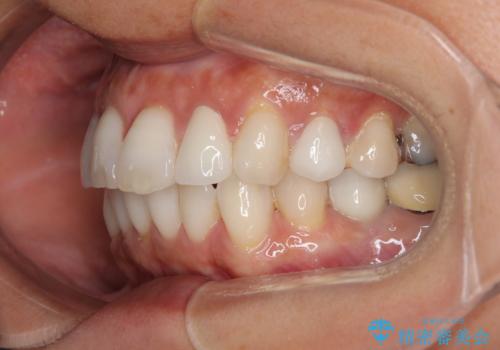

- 目立つ銀歯やむし歯、前歯のデコボコを気にして来院された患者様です。

デコボコはある程度改善できれば良いとのことでしたので、インビザラインの廉価版を用いて矯正治療を行うこととしました。

飛行機での通院であり、更にはご家族がの都合で海外に滞在されることも多いため、中等度の歯列不正に対応可能なインビザライン・モデレートパッケージを使用することとしました。

むし歯治療は、症状のある歯を矯正治療前に処置し、概ね歯列が整ったところで残りのは全て処置し、最後にインビザラインで歯列を仕上げることで、無駄なく治療を進めて行くこととしました。